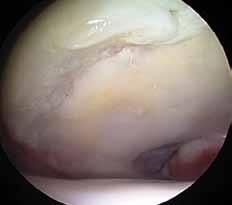

Fråga 2012-6 5p

Kvinna 57 årig tidigare frisk kvinna som inte tidigare har haft några problem med sina knäleder. En dag under vårens trädgårdsarbete känt smärtor i vänster knäled. Söker efter några dagar som jourfall då smärtorna snarast tenderar att öka. I status finner du lätt hydrops. Lätt rörelseinskränkning vänster jämfört med höger knäled. Lätt till måttlig ömhet medialt. Normal SR och CRP.

a. Differentialdiagnoser? (1p)

b. Hur handlägger Du patienten vid detta besök? (2p)

c. Hur utreder man ytterligare om patienten återkommer pga tilltagande besvär efter ett par veckor? (2p)

a. Troliga diagnoser är degenerativ meniskruptur/artros, spontan knäledsosteonekros eller insufficiensfraktur.

b. Noggrant knä- och höftstatus eventuellt slätröntgen och patientinformation om möjliga diagnoser. Smärtlindring och aktivitetsråd.

c. Vidare utredning med MR kan vara

indicerad speciellt för att kartlägga en eventuell osteonekros. Tc-scintigrafi kan också leda till rätt diagnos.